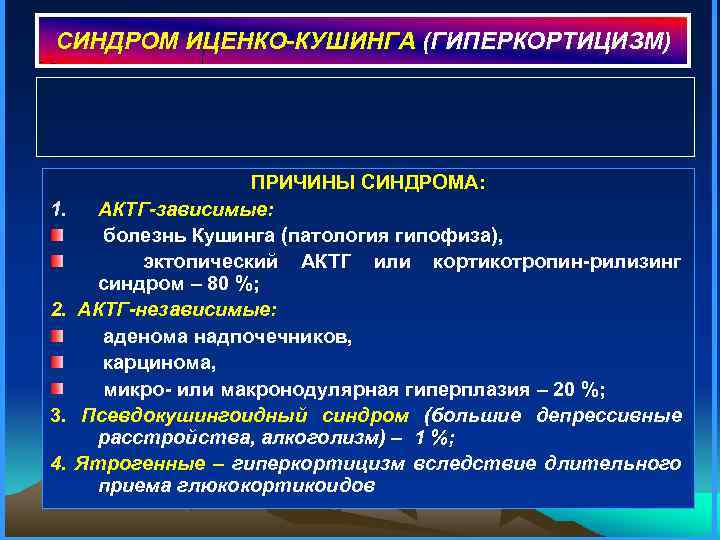

СИНДРОМ ИЦЕНКО-КУШИНГА (ГИПЕРКОРТИЦИЗМ) ПРИЧИНЫ СИНДРОМА: 1. АКТГ-зависимые: болезнь Кушинга (патология гипофиза), эктопический АКТГ или кортикотропин-рилизинг синдром – 80 %; 2. АКТГ-независимые: аденома надпочечников, карцинома, микро- или макронодулярная гиперплазия – 20 %; 3. Псевдокушингоидный синдром (большие депрессивные расстройства, алкоголизм) – 1 %; 4. Ятрогенные – гиперкортицизм вследствие длительного приема глюкокортикоидов

СИНДРОМ ИЦЕНКО-КУШИНГА (ГИПЕРКОРТИЦИЗМ) ПРИЧИНЫ СИНДРОМА: 1. АКТГ-зависимые: болезнь Кушинга (патология гипофиза), эктопический АКТГ или кортикотропин-рилизинг синдром – 80 %; 2. АКТГ-независимые: аденома надпочечников, карцинома, микро- или макронодулярная гиперплазия – 20 %; 3. Псевдокушингоидный синдром (большие депрессивные расстройства, алкоголизм) – 1 %; 4. Ятрогенные – гиперкортицизм вследствие длительного приема глюкокортикоидов